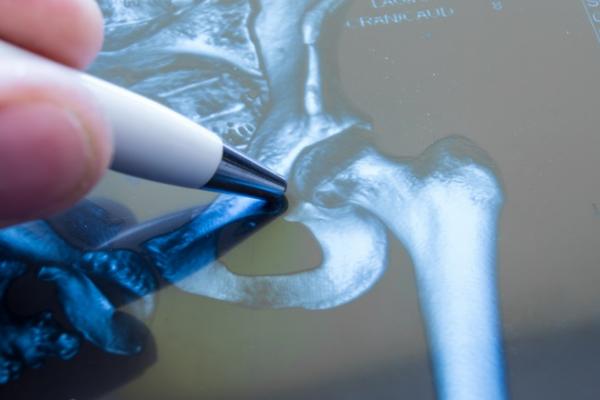

Stating that surgery is absolutely necessary for fractures that will prevent walking in the upper part of the leg, Orthopedics and Traumatology Specialist, said, "If a hip fracture that prevents walking has developed, that is, if there are fractures at the point connecting the patient's leg to the pelvis, the fractures in this area must be treated surgically. However, minor fractures of the pelvic bone itself can be healed with bed rest. After the surgery, we aim to put the patients on their feet as soon as possible."